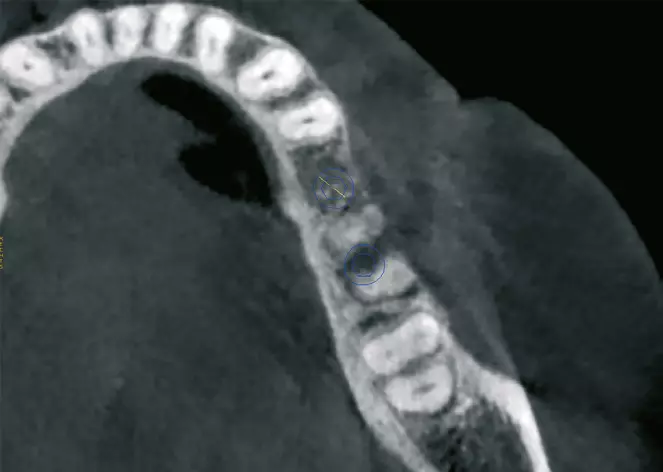

Der zweite Patientenfall beschäftigt sich mit einer Patientin Anfang 60, die sich mit einer verkürzten Zahnreihe bis zum Zahn 34 und dem Wunsch der Versorgung des III. Quadranten zu uns in die Praxis kam (Abb. 17a). Allgemeinanamnestisch besteht ein Diabetes mellitus, Sarkoidose und eine Primärprophylaxe mit ASS 100 mg. Die Zähne im III. Quadranten sind schon vor mehreren Jahren verloren gegangen, was die starke vertikale und horizontale Atrophie des Kieferkamms erklärt (Abb. 17b). Nach ausführlicher Aufklärung über alle Behandlungsmöglichkeiten und entstehende Kosten, entschied sich die Patientin für eine festsitzende Implantatversorgung mit drei Implantaten zum Ersatz der Zähne 45-47. Bei der Planung der Implantate zeigte sich das stark ausgeprägte horizontale und vertikale Knochendefizit, was den Knochenaufbau mit einem individuell geplanten Titangitter (Yxoss, ReOss) notwendig machte. Mittels DVT-Daten und entsprechender Planungssoftware wurde das 3D-Gitter individuell, entsprechend der anatomischen Verhältnisse und des benötigten Knochenvolumens, geplant und angefertigt (Abb. 17 c-e).